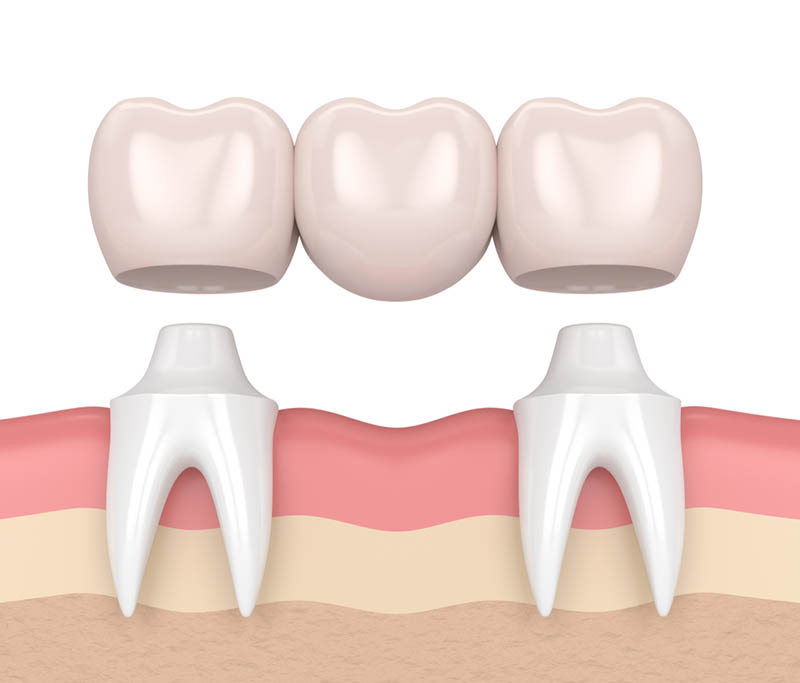

بریج دندان یکی از روش های قدیمی رفع مشکل نداشتن دندان است که از طریق آن می توان چای خالی یک یا چند دندان را پر کرد. پل دندان باعث ایجاد زیبایی بیشتر دندان ها می شود، چرا که با پر کردن فواصل بین دو دندان نقش بسزایی در افزایش زیبای طرح لبخند دارد. این روش که از اسمش پیداست (بریج دندان)، مثل یکی پل عمل کرده و از طریق قرار دادن روکش مصنوعی و دندان مصنوعی، دو دندان را به یکدیگر وصل میکند. دندان مصنوعی با کمک دو دندان اطراف روکش شده سر جای خود محکم باقی می ماند.

وقتی که یکی از دندان های از بین می رود ولی دندان های اطراف آن سالم است، دندان پزشک از روش بریج دندان استفاده کرده و باعث میشود تا شکل دندان های که از نظر ظاهری ناخوشایند است را به فرم روز اولیه خود برگرداند. جنس دندان مصنوعی به کار رفته می تواند از جنس سرامیک، طلا و یا آلیاژهای دیگر باشد.

برای پر کردن جای خالی بین دو دندان و حمایت دندان مصنوعی به کمک دو دندان اطراف لازم است تا مینای این دو دندان اطراف برش داده شود تا از این طریق بتوان روکش ها را بر آن سوار کرد، این عمل بزرگترین عیب بریج دنـدان است چرا که در اینصورت بخش زیادی از بافت های سالم دندان از بین رفته و دیگر نمی توان این بافت ها را به حالت اول برگرداند، به دلیل اینکه این بخش دیگر رشد نمیکند و توانایی بازسازی مجدد را ندارد، در صورتی که در روش ایمپلنت (کاشت دندان)، هیچ آسیبی به دندان های مجاور وارد نمی شود.

- در مرحله اول در صورتی که دندان های اطراف فضای خالی، سالم باشد دندان پزشک آن دو دندان را برای قرار دادن روکش آماده می کند اما اگر این دو دندان به منظور حمایت از دندان مصنوعی مناسب نباشد، دندان پزشک مجبور می شود از طریق جراحی، ایمپلنت هایی را درون لثه قرار دهد.

- در مرحله دوم دندان پزشک از دستگاهی برای تشکیل روکش دندان های اطراف فضای خالی و دندان مصنوعی استفاده میکند. به روکش دندان و دندان مصنوعی، بریج گفته می شود.